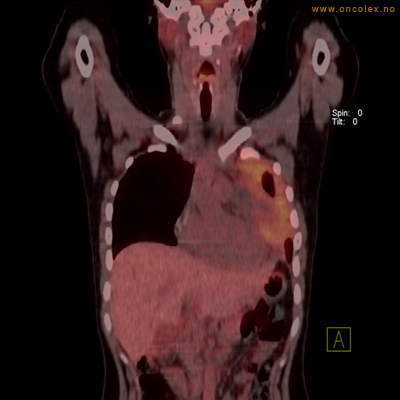

Vev som tar opp mer radioaktivt stoff, synes som hvite områder som lyser opp mer i forhold til annet vev som tar opp mindre sukker.

Moderat opptak av FDG i bløtvevssarkom venstre halvdel av brystkassen. Områder med lavere opptak antas å skyldes dels betennelse som skyldes svulst, dels svulstnekrose.

Kraftig opptak i svulst i lunge.

Lungekreft med spredning til lymfeknute i lungehilus.